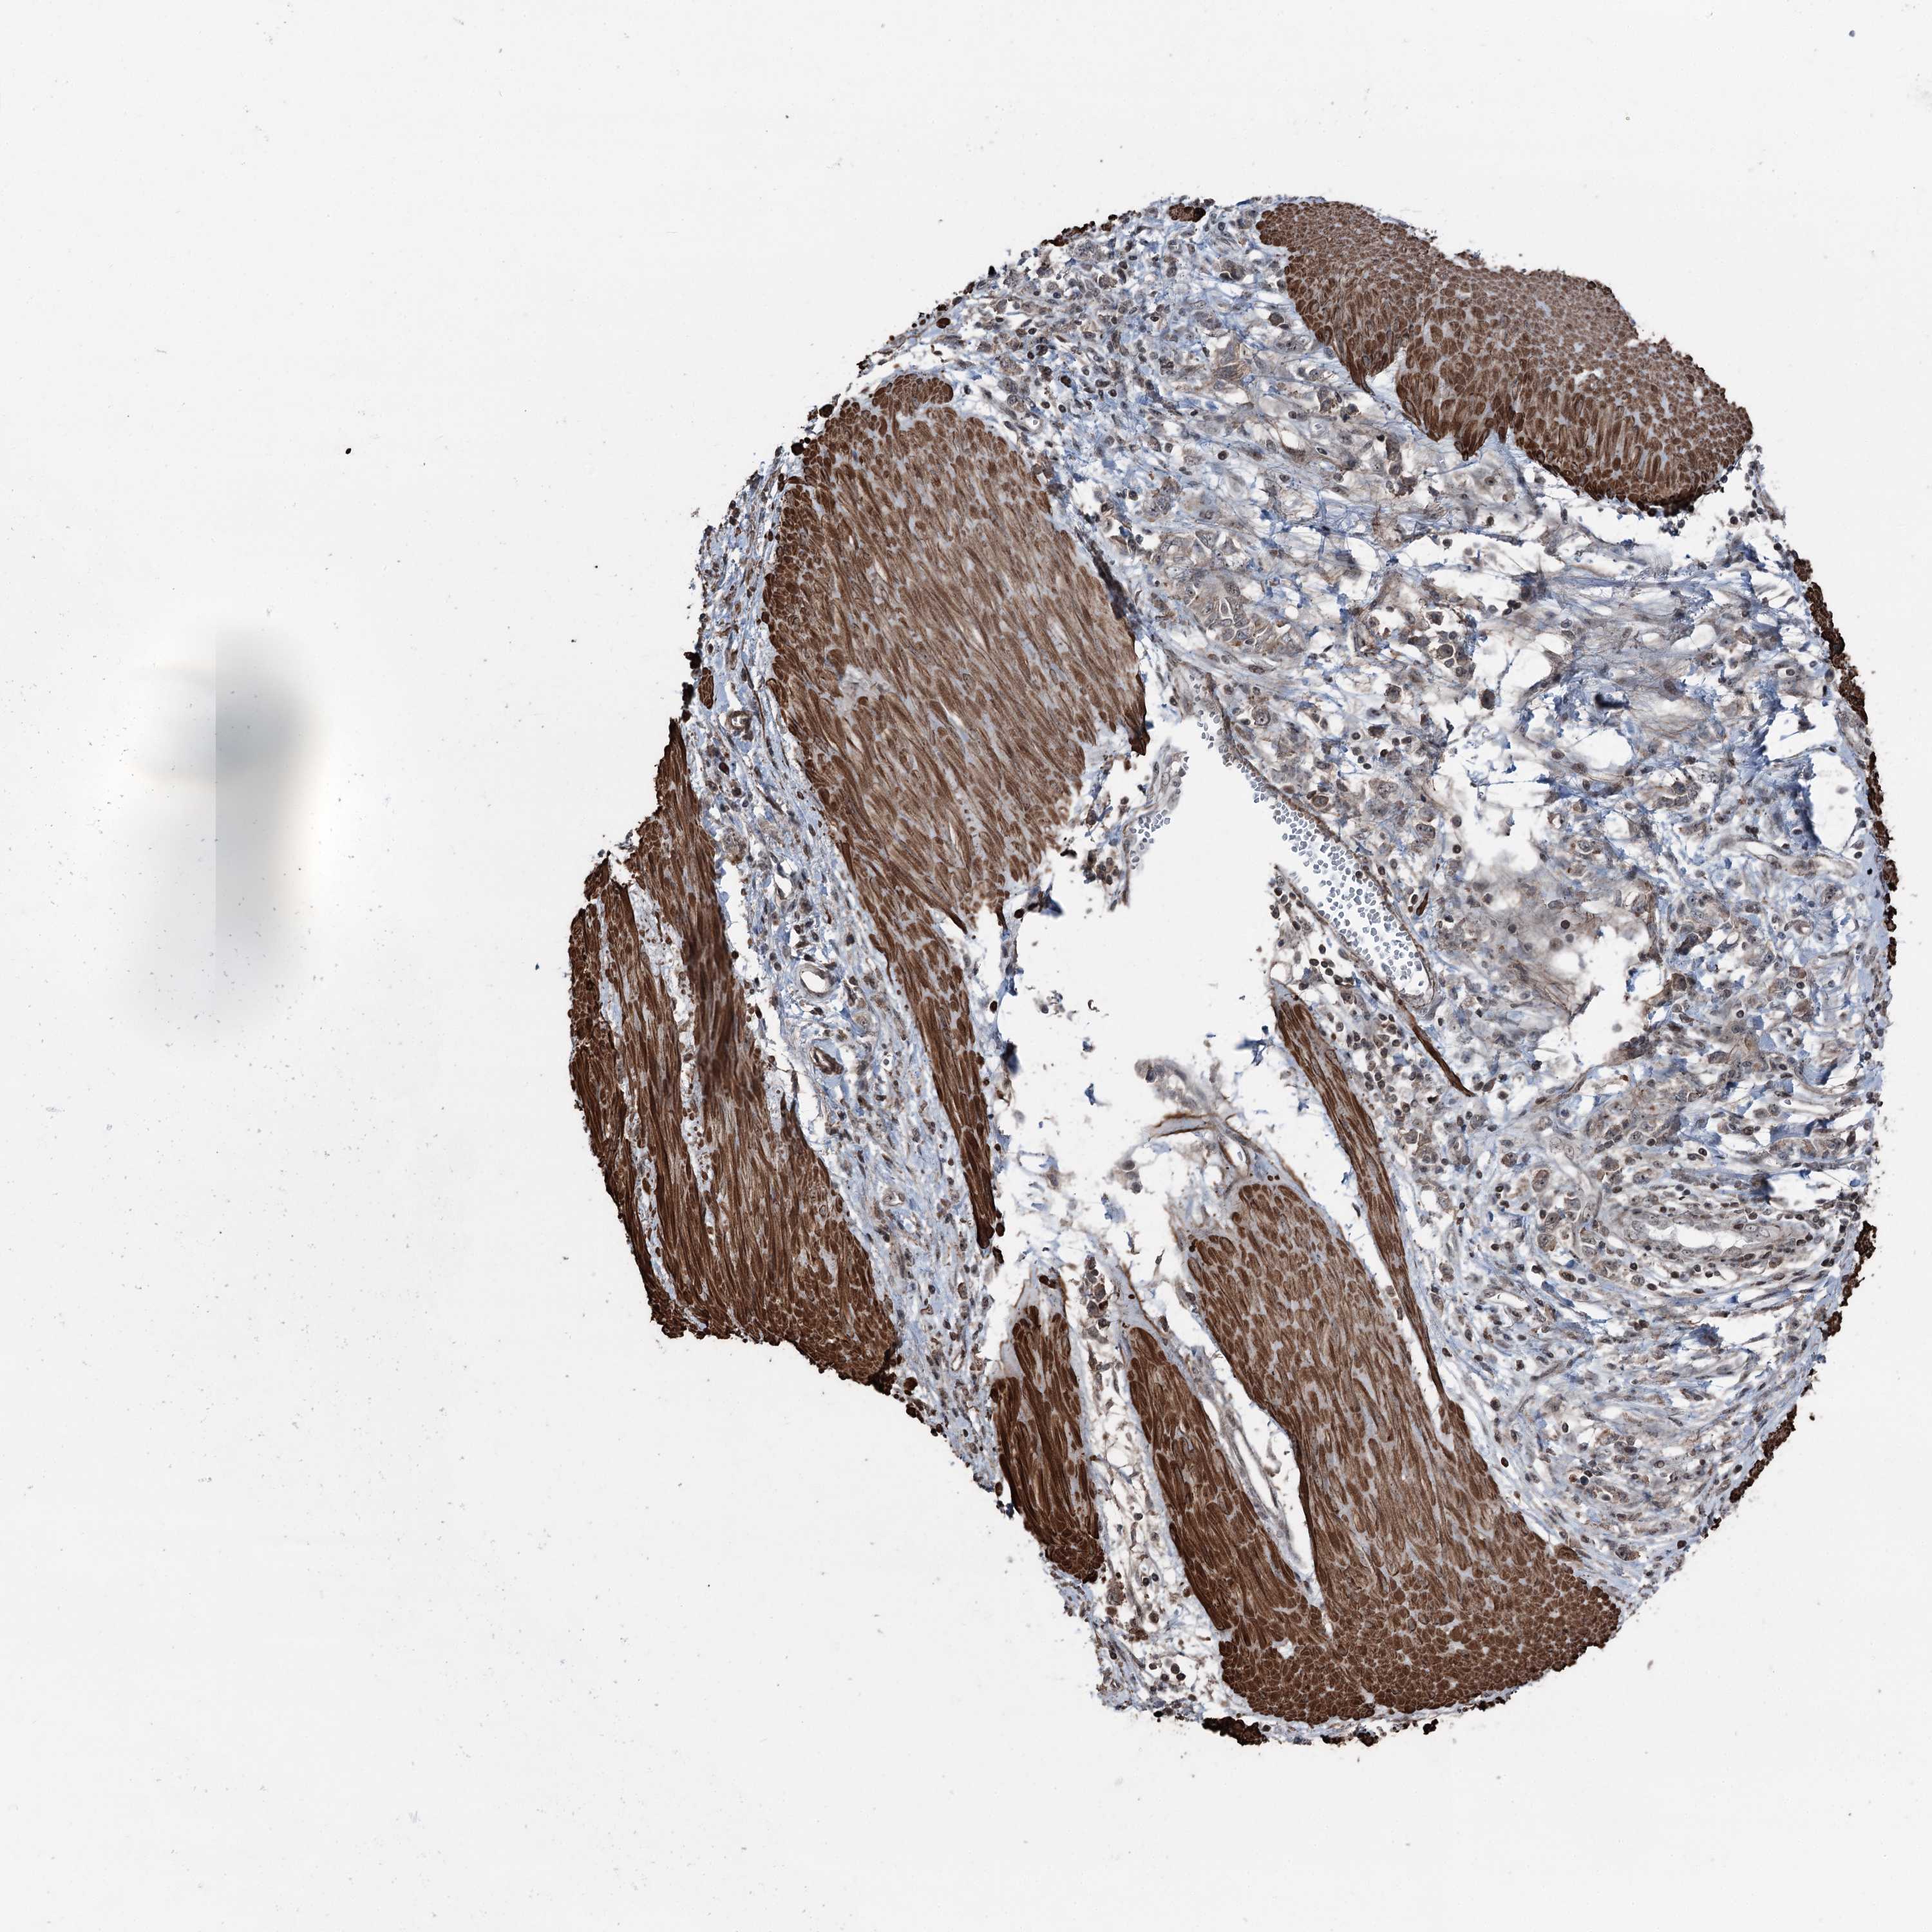

STOMACH CANCER - Protein expressioni

A mouse-over function shows sample information and annotation data. Click on an image to view it in a full screen mode. Samples can be filtered based on level of antibody staining by selecting one or several of the following categories: high, medium, low and not detected. The assay and annotation is described here.

Note that samples used for immunohistochemistry by the Human Protein Atlas do not correspond to samples in the TCGA dataset.

Antibody stainingi

Antibody staining in the annotated cell types in the current human tissue is reported as not detected, low, medium, or high, based on conventional immunohistochemistry profiling in selected tissues. This score is based on the combination of the staining intensity and fraction of stained cells.

Each image is clickable and will lead to virtual microscopy that enables deeper exploration of all samples and also displays staining intensity scores, fraction scores and subcellular localization as well as patient and tissue information for each sample.

Antibody HPA038704

Staining

High

Medium

Low

Not detected

Intensity

Strong

Moderate

Weak

Negative

Quantity

>75%

75%-25%

<25%

None

Location

Nuclear

Cytoplasmic/membranous

Cytoplasmic/membranous,nuclear

Adenocarcinoma, NOS